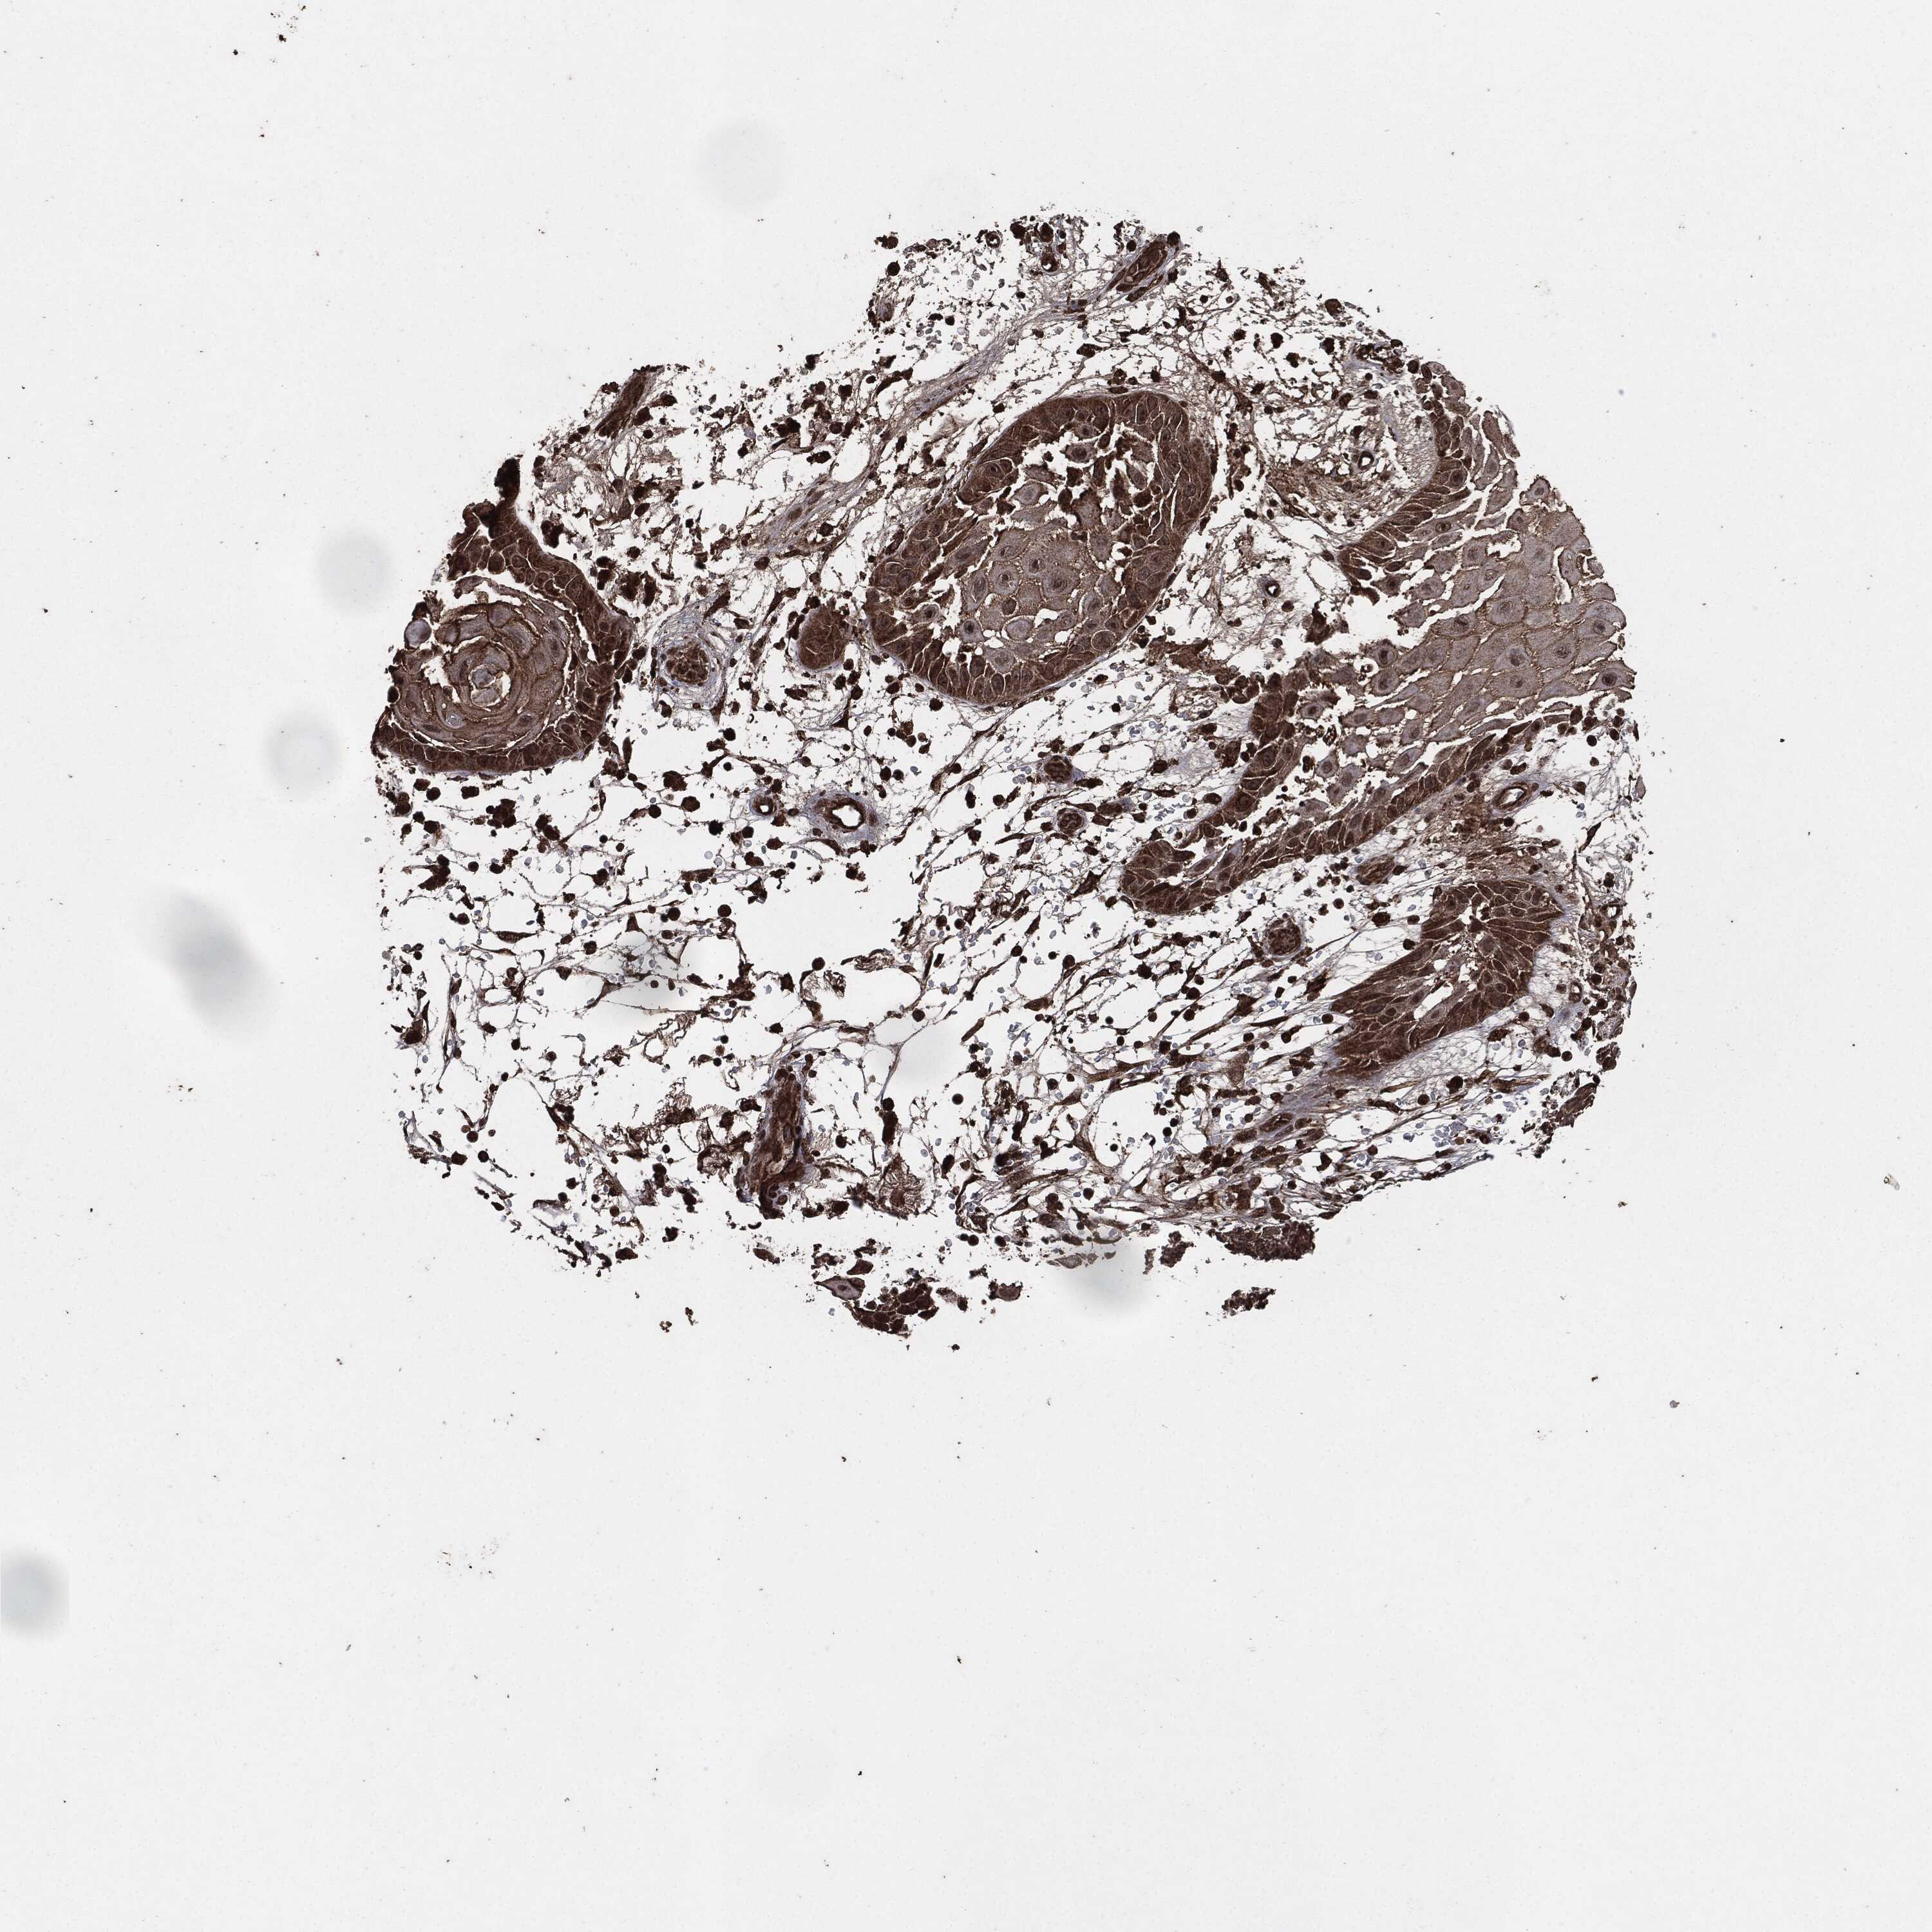

SKIN CANCER - Protein expressioni

A mouse-over function shows sample information and annotation data. Click on an image to view it in a full screen mode. Samples can be filtered based on level of antibody staining by selecting one or several of the following categories: high, medium, low and not detected. The assay and annotation is described here.

Each image is clickable and will lead to virtual microscopy that enables deeper exploration of all samples and also displays staining intensity scores, fraction scores and subcellular localization as well as patient and tissue information for each sample.

HPA001200

Staining

High

Medium

Low

Not detected

Squamous cell carcinoma, NOS

Basal cell carcinoma

Squamous cell carcinoma in situ, NOS

Squamous cell carcinoma, metastatic, NOS